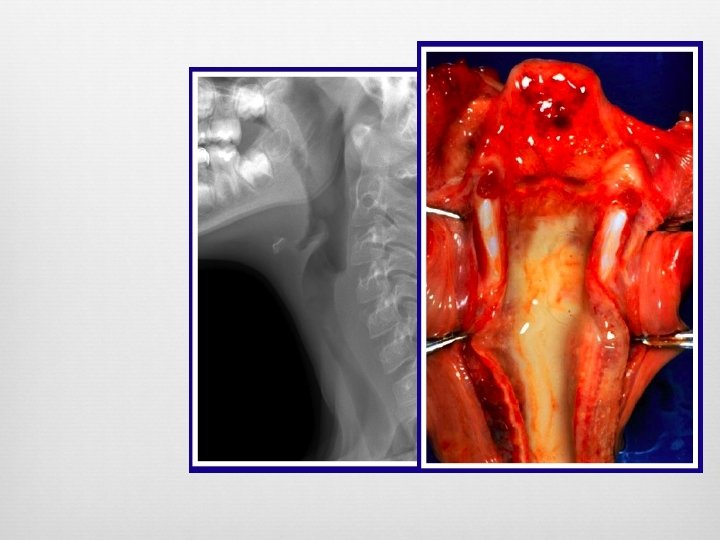

Epiglottitis Enlarged epiglottis Loss of valecular airspace Thickened aryepiglotic folds Distended hypopharynx Straightening of the cervical spine Sensitivity (38 -88%) Specificity (78%) Croup and epiglottitis: a radiologic study. AU Stankiewicz JA; Bowes AK SO Laryngoscope 1985 Oct; 95(10): 1159 -60. Epiglottitis and croup. AU Sobol SE; Zapata S SO Otolaryngol Clin North Am. 2008 Jun; 41(3): 551 -66, ix. Adult epiglottitis: the Toronto Hospital experience. AU Solomon P; Weisbrod M; Irish JC; Gullane PJ SO J Otolaryngol. 1998 Dec; 27(6): 332 -6.

Foreign Body Visualization of radiopaque FB Widened pre-vertebral shadow Loss of lordosis Location Esophagus – coronal plane Trachea – sagittal plane (best seen on lateral)